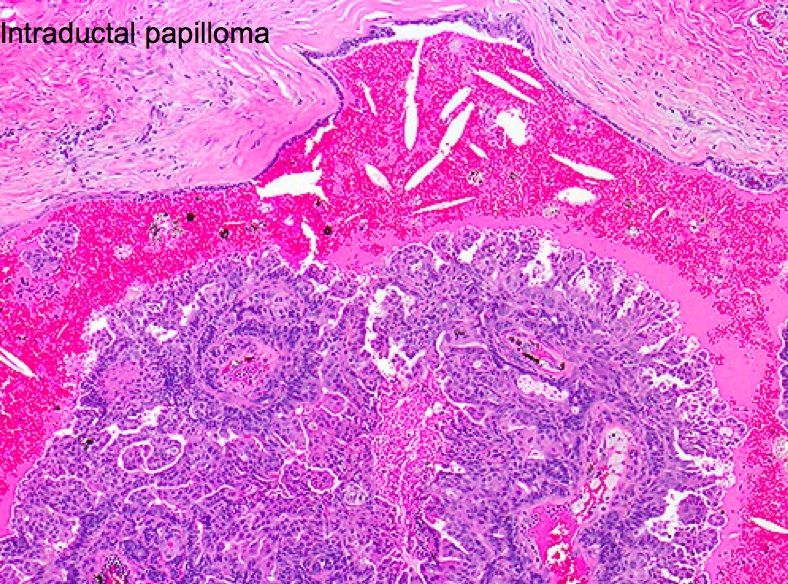

Intraductal Papilloma

_Is a benign papillary growth, usually into a large lactiferous duct, and it is the most common cause of bloody nipple discharge in premenopausal women (<50).,

_Is characterized by fibrovascular projections lined by epithelial (luminal) and myoepithelial cells..

Contrast this with papillary carcinoma (also bloody discharge), where fibrovascular projections possess epithelial cells without underlying myoepithelial cells. The risk of papillary carcinoma increases with age, thus, it is more commonly seen in postmenopausal women.

both layers of cells

myoepithelial: contractile

luminal: milk production